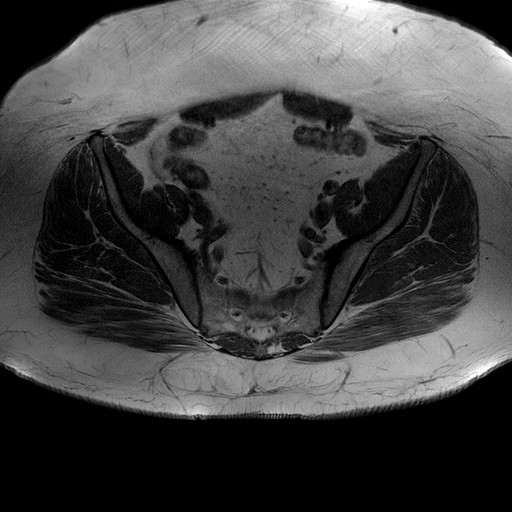

Esami: RMN BACINO

T1W_TSE

Evidenti e simmetriche alterazioni osteofitosiche in regione coxo femorale con riduzione delle rime articolari. Degenerazione completa del cercine glenoideo. Non attuali segni di versamento articolare. Non segni di edema osseo che escludono attuale algodistrofia od osteonecrosi. Lieve e simmetrica riduzione del trofismo della muscolatura glutea.